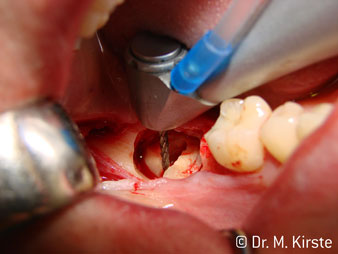

Speaking of working quickly: the instrument can achieve up to 100,000 rpm while a very professional cooling system and small attachment head cover all aspects relating to thermal effects and unobstructed work.

The professional design of the bearings inside the handpiece head guarantees quiet running of the bur; this makes for an impressively atraumatic cut in the separation of tooth and root (fig. 4-9).